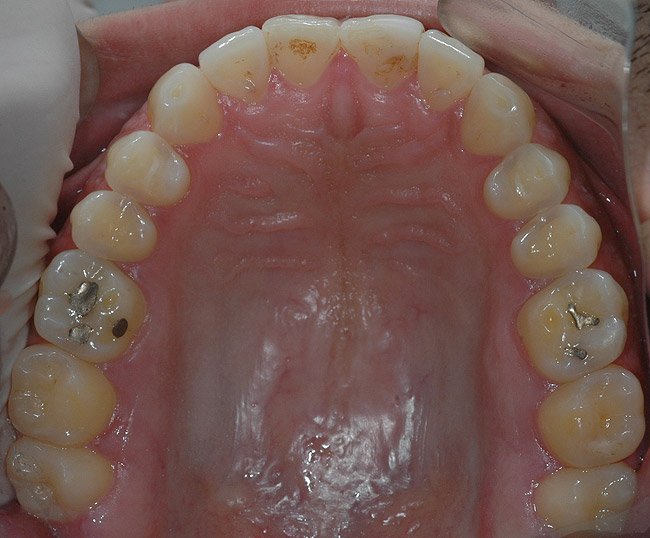

În cursul examinării clinice s-a notat o igienă orală satisfăcătoare. Pacientul prezenta coroziunea suprafeţelor ocluzale şi orale la dinţi maxilari şi mandibulari posteriori (fig. 1). Avea, de asemenea, arii expuse de ţesut dentinar (fig. 3) şi restaurări din amalgam compromise în lipsa sprijinului adecvat.

Toţi dinţii posteriori au fost reabilitaţi cu restaurări directe pe bază de răşină şi la nivelul hemiarcadei controlaterale, într-un mod similar celui descris anterior, restabilind astfel dimensiunea verticală (fig. 10, 11). S-a efectuat ajustarea ocluzală şi proximală, pentru a obţine contururi adecvate.

S-a restabilit ghidajul anterior prin înălţarea cu aproximativ 2mm a muchiei incizale la dinţii mandibulari frontali (de la canin la canin). S-a efectuat restaurarea caninului 2.3. impusă de forma necorespunzătoare a acestuia. S-au folosit aceleaşi culori şi materiale şi pentru restaurarea dinţilor frontali (fig. 12). S-a creat o nouă gutieră ocluzală pentru a ajuta la asigurarea unei bune longevităţi clinice. Pacientul a beneficiat de instructaj de igienă orală.